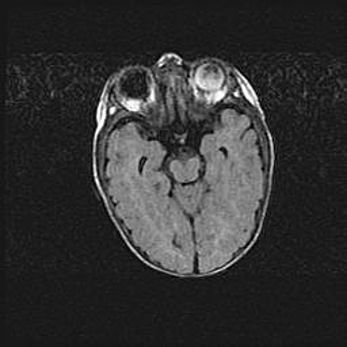

Лейкомаляция с кистозно-глиозной дегенерацией головного мозга.

Возраст: 2 месяца 25 дней

Вес: 6400 г

Окружность головы: 40 см

Срок гестации: 41 неделя

Лейкомаляцию относят к ишемически-гипоксическим повреждениям головного мозга, диагностируемым у новорожденных. При лейкомаляции в головном мозге обнаруживают очаги некроза, возникшие после тяжелой гипоксии и нарушения кровотока. В процессе морфогенеза очаги проходят три стадии: 1) развития некроза, 2) резорбции и 3) формирования глиозного рубца или кисты. Перивентрикулярная лейкомаляция (ПЛ) встречается примерно в 12% случаев среди новорожденных, обычно – у недоношенных детей, причем, частота ее зависит от массы, с которой младенец появился на свет. Наибольшее число малышей страдает лейкомаляцией, если масса при рождении 1500-2500 г.